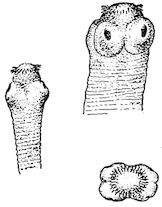

Fig. 9.—C, horn; P, modified skin forming the keratogenous membrane; O, horn core, exhibiting a double sinus.

(2.) The horn-secreting membrane is formed by the skin, which undergoes special development around the base of the horn and comes to resemble that of the coronary band, from which the hoof or claw is secreted. The band is about one-fifth of an inch in breadth. The papillæ of the dermis are specially developed at this point, and the epithelium which they secrete eventually forms the horn.

The internal surface of the growing horn is adherent to the horn core through the medium of another tissue formed by a specially differentiated periosteum which is continuous with the periosteum covering the frontal bone. It is not a true periosteum, but a vascular tissue formed of papillary layers analogous to those of the podophyllous tissue of the ox’s claw or horse’s hoof.

This keratogenous membrane receives a rich vascular supply from the arterial circle formed at the base of the horn core by a division of the external carotid, the blood conveyed by which is freely distributed to the enlarged papillæ. The great vascularity of these parts 23explains why lesions of the horns are often followed by such profuse bleeding.

(3.) The horn secreted by the papillæ of the horn band (which is analogous to that of the coronary band of the horse) forms a cone varying in its curve in various breeds. Its base is hollow, and contains little depressions holding the papillæ from which the horn is secreted. From its base up to the end of the horn core the walls progressively increase in thickness. From this point it is solid; in a fully-grown horn the bone does not extend more than one-half or two-thirds of the entire length.